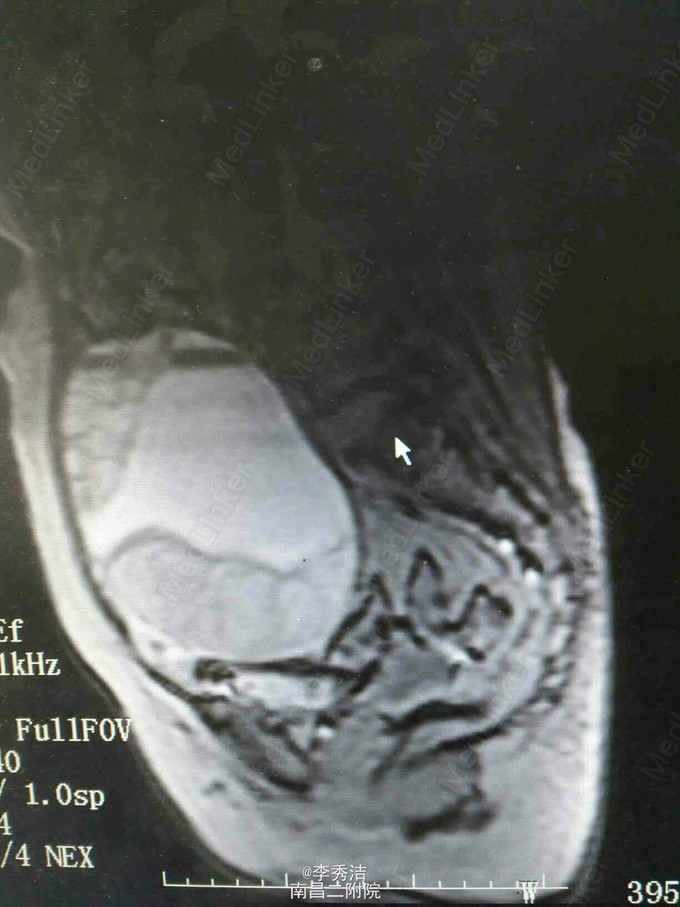

患者64岁,因“下腹部疼痛不适3月”入院。

查体:腹隆,可及一实性包块,上界平脐,下界至耻骨联合,两侧达腹直肌外缘,活动欠佳,无压痛。妇科检查:外阴:萎缩,阴道:畅,潮红,少许淡黄色分泌物,异味重。宫颈萎缩,宫体扪不清,盆腔扪及一巨大包块,达脐,如孕4月子宫大小,活动差,无压痛,实性,肛诊:于直肠前壁距肛门约7㎝处可及一外压性肿块,实性,质硬,指套无血染,直肠粘膜光滑。糖类抗原CA125-36.00U/mL。我院盆腔磁共振示盆腹腔巨大多房囊性占位,考虑附件来源肿瘤病变,粘液性囊腺瘤可能。